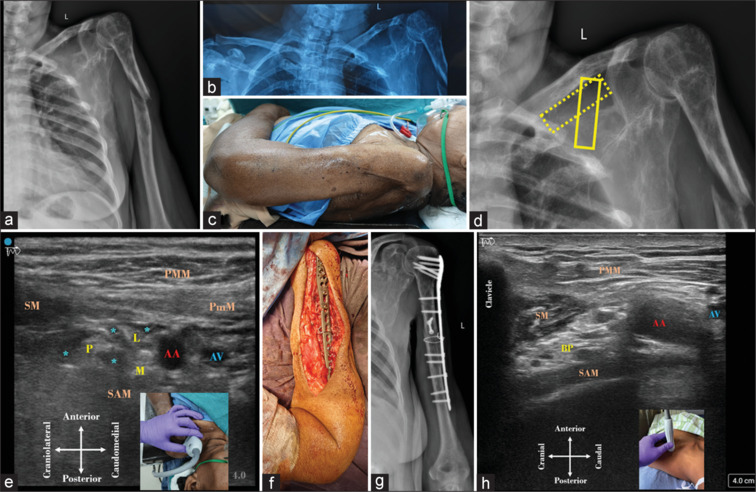

Modified costoclavicular block: A redemption shaped by fate, not choice!